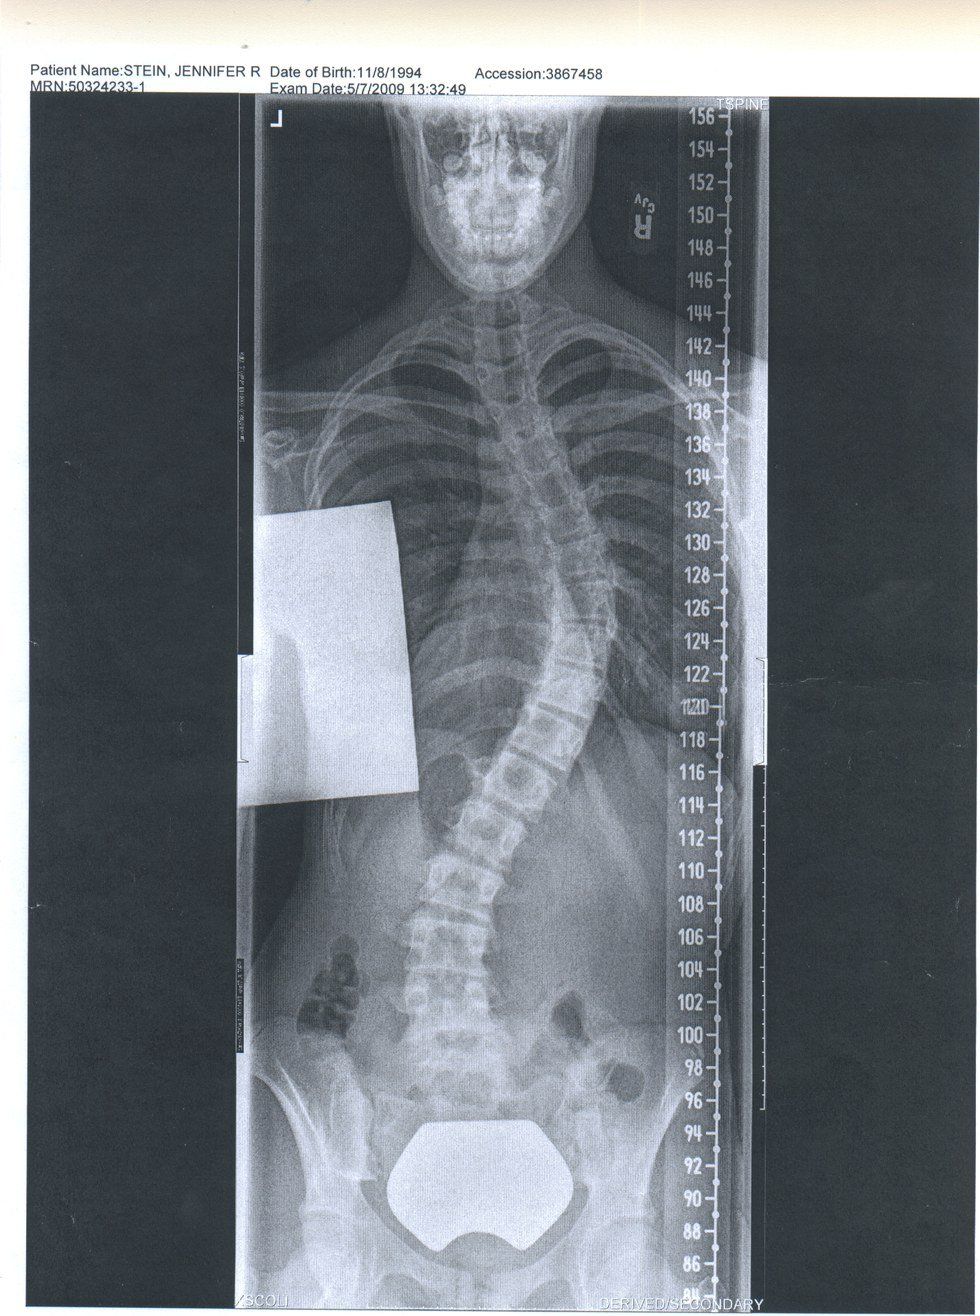

Scoliosis is a curvature of the spine, which tend to be prevalent in girls, occurring around puberty. Most normal humans don't have perfectly straight spines, and at least some degree of curve. I've had many people tell me, "Oh I have a cousin/sister/aunt/mom/friend with that!" which is due to it's commonality. Most cases need no treatment, and if a treatment is needed, the type depends on the severity of the curve. The severity is measured by the degree that the curve is. Milder cases can be corrected by wearing a brace, and strengthening the muscles that surround the vertebrae. In extreme cases, corrective surgery can be performed. I was in eighth grade December 2008, and my doctors told me that the only way to fix my curved spine was surgery because I had a 50 degree curve, and I could opt to live with it, or choose when to have the surgery, which could have been a couple years down the road.

It all happened so fast. The pain in the fall, the diagnosis in the winter, and by spring I had my operation physical, I had blood drawn for the dialysis machine I would be hooked up to to keep my blood running during my surgery, and my last x-rays before the surgery. My curvature had increased to 55 degrees. In less than a year I had never heard of scoliosis and then I was having a incredibly risky surgery.